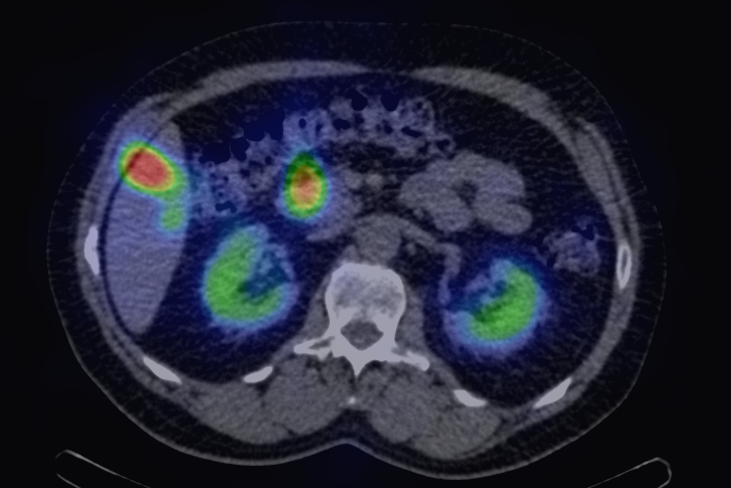

21.4.1.1. PET

The most significant modality among direct methods is FDG PET or PET-CT that – by being able to visualize viable tumor tissue – provides such information that the other noninvasive modalities are unable to do.

The most common clinical use of FDG-PET is in the form of whole-body scan, with oncologic indications. The majority of malignant tumors operate with higher energy consumption and show an increased glucose metabolism, consequently an increased uptake of FDG. The grade of malignancy is usually proportional to the rate of uptake. This method is useful in oncologic diagnostics, since it is capable to differentiate benign lesions from malignant ones. Whole-body PET imaging is capable to detect the primary tumor with local nodal metastases as well as distant metastatic lesions (staging) in one examination. (Figure 10.)

Test iframe

a

Image

b

c

d

10. Ewing’s sarcoma in the right humerus. Staging FDG PET-CT. PET Maximum Intensity Projection (MIP) image (a), transversal (b,c) and coronal (d) plane fused PET-CT images. Multiplex metastatic process with nodal, lung and bone involvement.